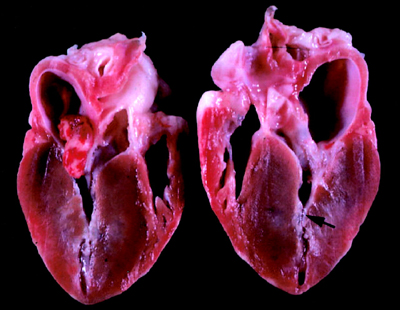

Este o forma de cardiomiopatie dilatativa care apare in

peripartum la femeile anterior sanatoase. Se defineste

ca disfunctie de ventricul stang inexplicabila, care

apare in ultima luna de sarcina ori pana la 5 luni dupa

nastere. Aceasta definitie vrea sa excluda formele

preexistente de cardiomiopatie dilatativa(DCM), care

pot fi prezente dar nesuspectate inainte de sarcina si

este probabil ca sarcina sa le agraveze si sa devina

manifeste anterior ultimei luni de sarcina. Sunt putine

date in literatura referitoare la DCM si sarcina, posibil

pentru ca pacientele diagnosticate anterior sunt

descurajate sa ramana insarcinate. Cazurile raportate

descriu de obicei o deteriorare marcata.